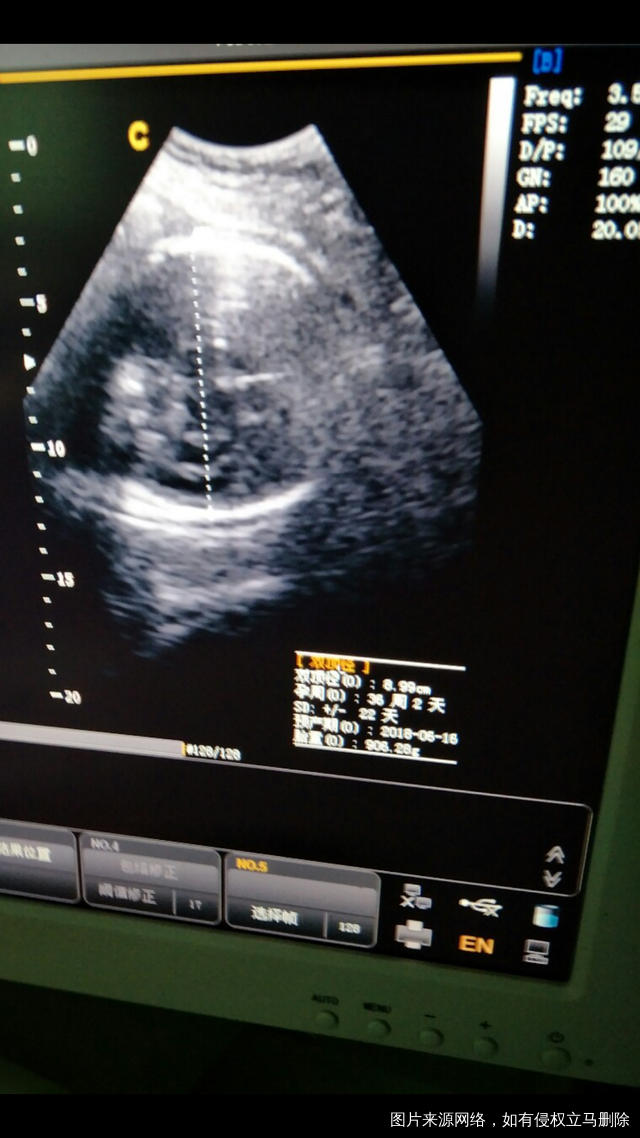

35周+查的,SD+/–:22天是什么意思,胎重906.2g不明白怎么回事